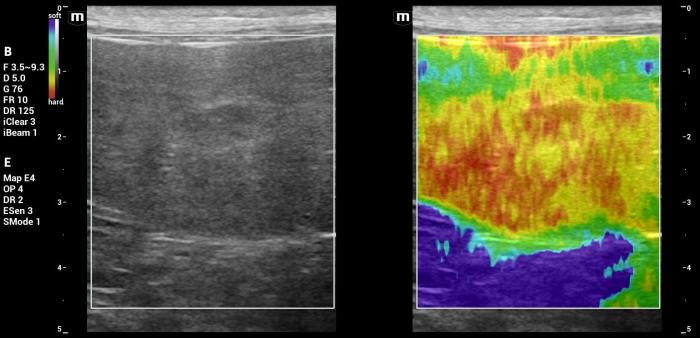

Hallazgos elastográficos (Natural Touch Elastography®): el nódulo presentó una rigidez marcadamente aumentada respecto del parénquima esplénico circundante, con patrón elastográfico heterogéneo (“dureza mixta”), caracterizado por áreas internas de elevada velocidad de onda de corte (Figura 26-27).

Este comportamiento se alinea con los hallazgos reportados para lesiones malignas esplénicas, que tienden a presentar valores superiores a 3 m/s según la evidencia publicada5.

Las mediciones fueron consistentes entre sí y no mostraron artefactos relevantes, lo que respalda la confiabilidad del hallazgo elastográfico.

Interpretación:la combinación de ecogenicidad mixta, presencia de focos hiperecoicos puntiformes, deformación esplénica y vascularización positiva plantea un patrón ecográfico compatible con neoplasia. La rigidez significativamente elevada respecto del parénquima esplénico normal constituye un hallazgo congruente con lesiones malignas, tal como se ha documentado en estudios previos5.

En este caso, el comportamiento elastográfico resultó altamente concordante con el diagnóstico final de linfoma folicular, reforzando la utilidad de la elastografía mediante NTE para apoyar la sospecha diagnóstica en el contexto de masas esplénicas sólidas.